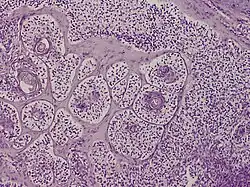

Trichilemmal carcinoma

Trichilemmal carcinoma is a cutaneous condition reported to arise on sun-exposed areas, most commonly the face and ears.[1]: 674